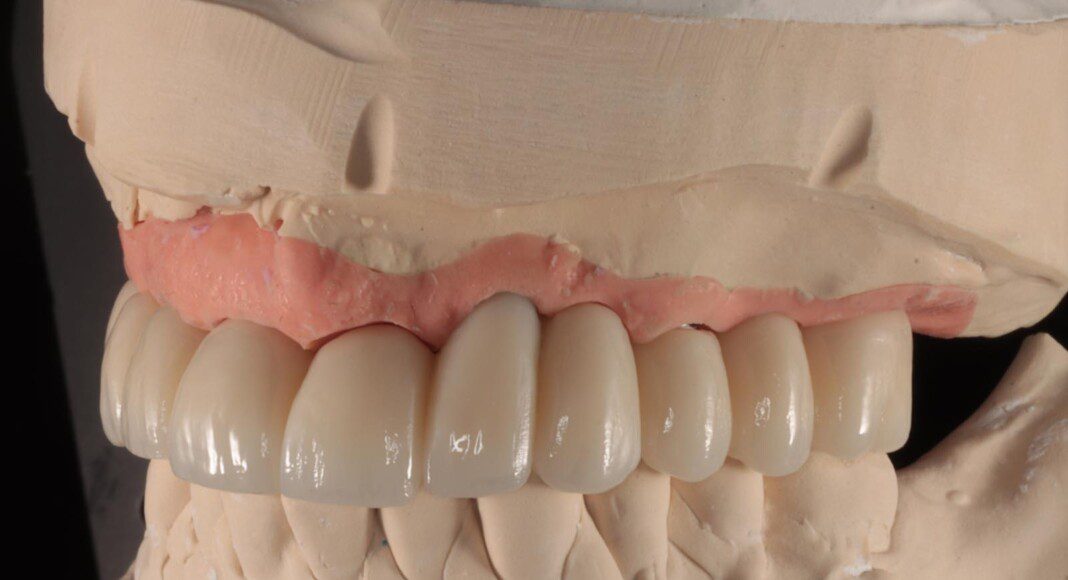

Prototype try-in. This patient was much more particular than we expected. Therefore, we made a very detailed prototype for everyone to evaluate closely. Pictures taken from all angles.